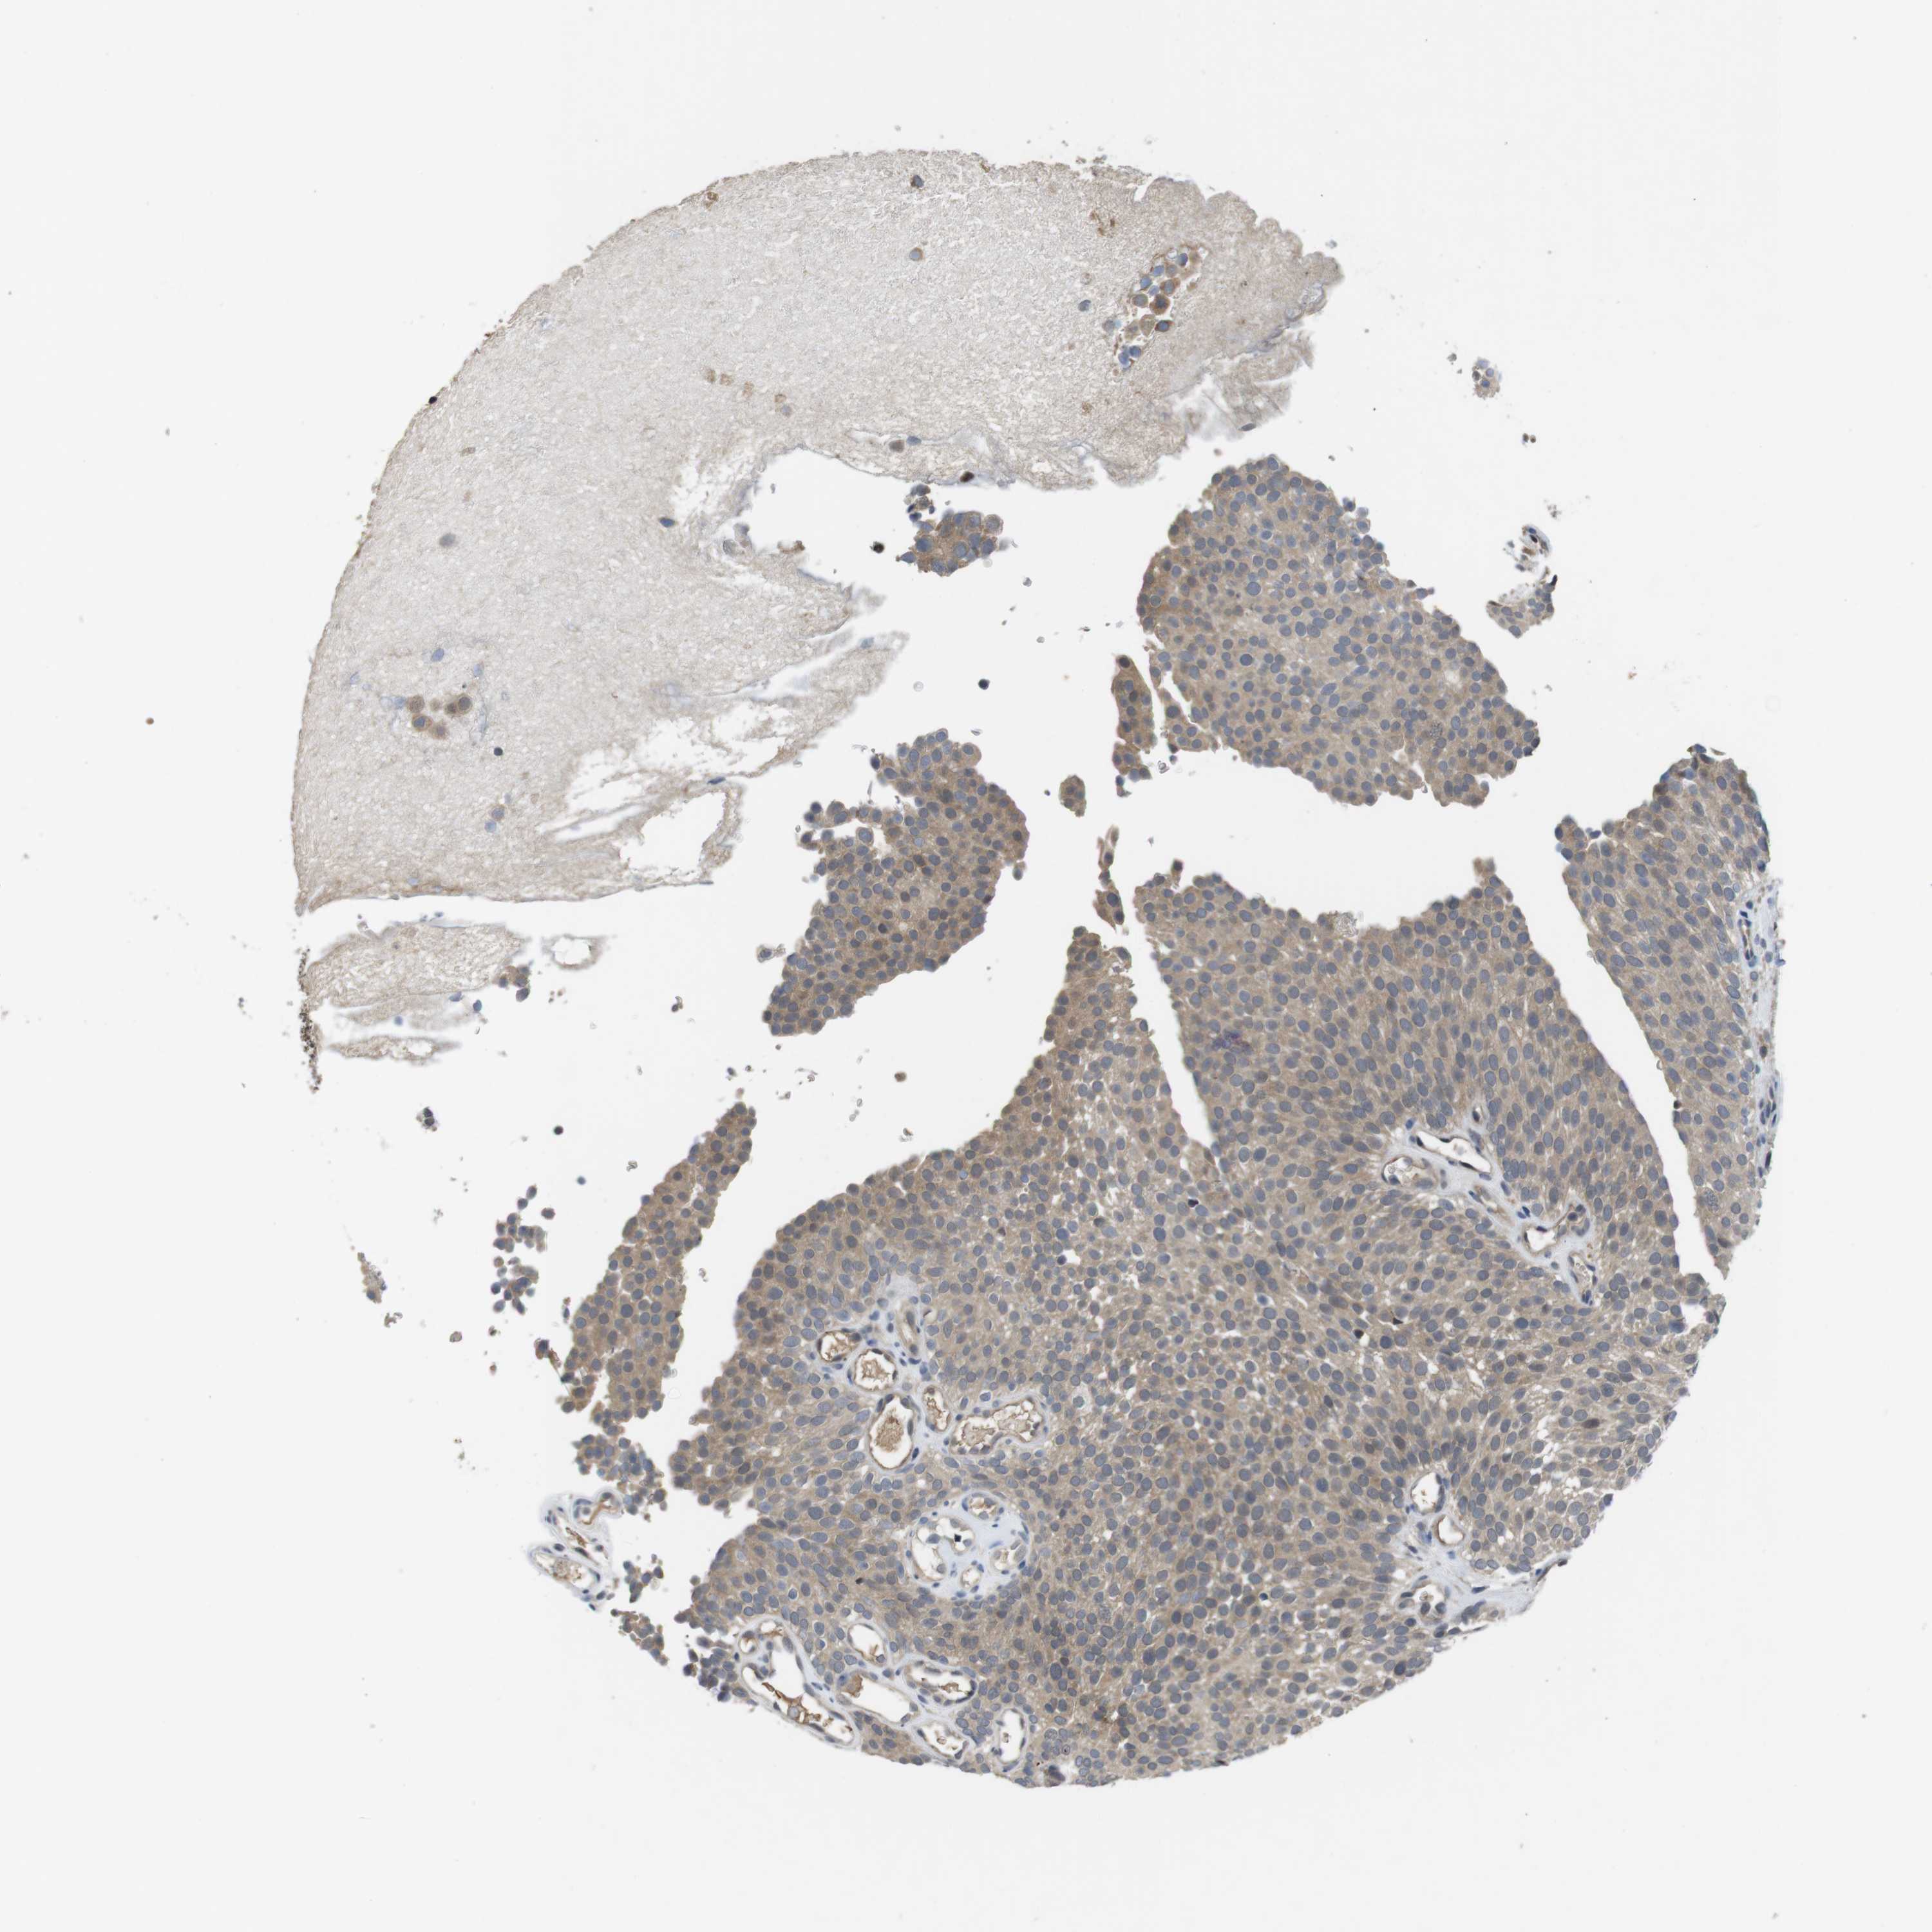

UROTHELIAL CANCER - Protein expressioni

A mouse-over function shows sample information and annotation data. Click on an image to view it in a full screen mode. Samples can be filtered based on level of antibody staining by selecting one or several of the following categories: high, medium, low and not detected. The assay and annotation is described here.

Note that samples used for immunohistochemistry by the Human Protein Atlas do not correspond to samples in the TCGA dataset.

Antibody stainingi

Antibody staining in the annotated cell types in the current human tissue is reported as not detected, low, medium, or high, based on conventional immunohistochemistry profiling in selected tissues. This score is based on the combination of the staining intensity and fraction of stained cells.

Each image is clickable and will lead to virtual microscopy that enables deeper exploration of all samples and also displays staining intensity scores, fraction scores and subcellular localization as well as patient and tissue information for each sample.

Antibody HPA001464

Antibody CAB010209

Urothelial carcinoma, Low grade

Urothelial carcinoma, High grade